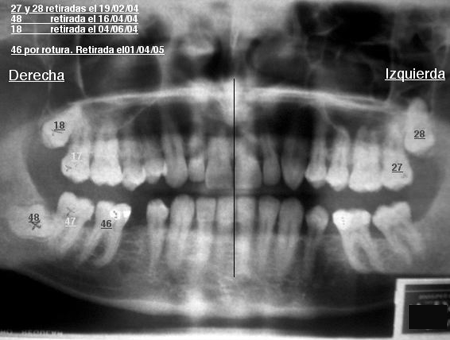

Algunos ejemplos de imágenes digitales

Pulse en las imágenes para ver la ampliación

dientes